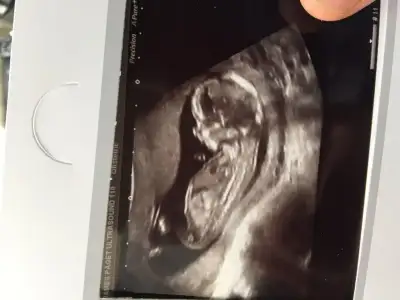

Gijnij merhaba ben seni ve buranin sıkı takipcilerindenim benim de 2 kizim var ALLAH nasip ederse 3 cuye hamileyim 14 haftalik rica etsem resimi eklesem bana yorum edermisin image.webp

ben mesaj atmıştım sana ama sorun oldu gitmedi sanırım. bu fotoda ben nubu çözemedim canım

Sagolasin canim yorumun icin ben 13 haftalikken gittigimde ozeldeki doktor yuzde yetmis erkek demisti 2 li icinde devlete gittim soylemedi ondan merak ettim sordum cnm bu arada senin bana msjin gelmedi gelseydi soylerdim cnm

Bebeğin kız canım hayırlı olsun inşallah

bak buda bacak arası. ama video çekmiştik sanki pipi var gibi geldi bana. acaba kordon mu o? çok kalındı zaten keşke videoyu gönderebilsem sana :).. bu arada yorumun için çok teşekkür ederim canım:KK68:

• tp.webp

tp.webp

12,6 KB · Görüntüleme: 194

Canım kızda da erkekte de bu haftalarda çıkıntı oluyor sadece kızın çıkıntılı karşıya bakıyor erkeğin yukarı doğru senin o pipi gibi gösterdiğin karşıya bakıyor kız gibi yani yinede yanılma payı vardır mutlaka